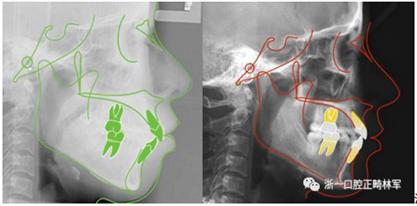

治療前后側(cè)位片對(duì)比

11.png

治療前后頭影測(cè)量重疊圖(綠色治療前,紅色治療后)

12.png